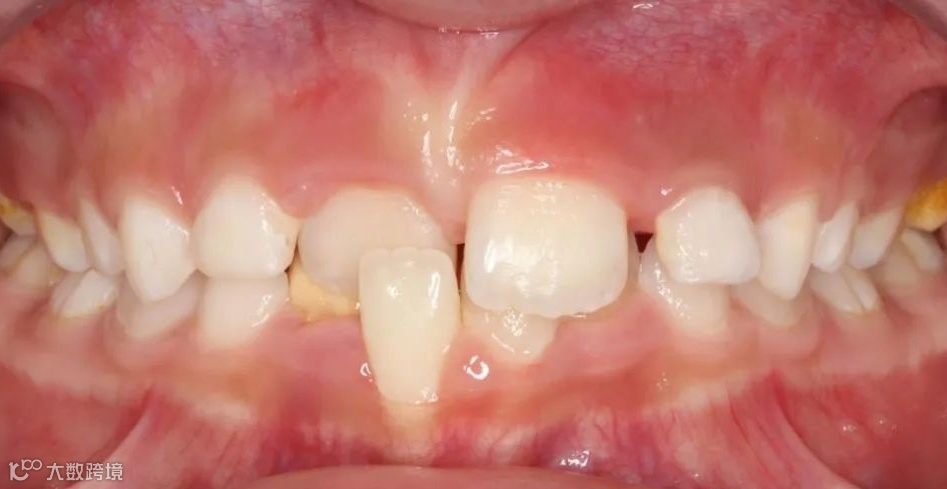

乳牙反𬌗治疗前

乳牙反𬌗治疗后